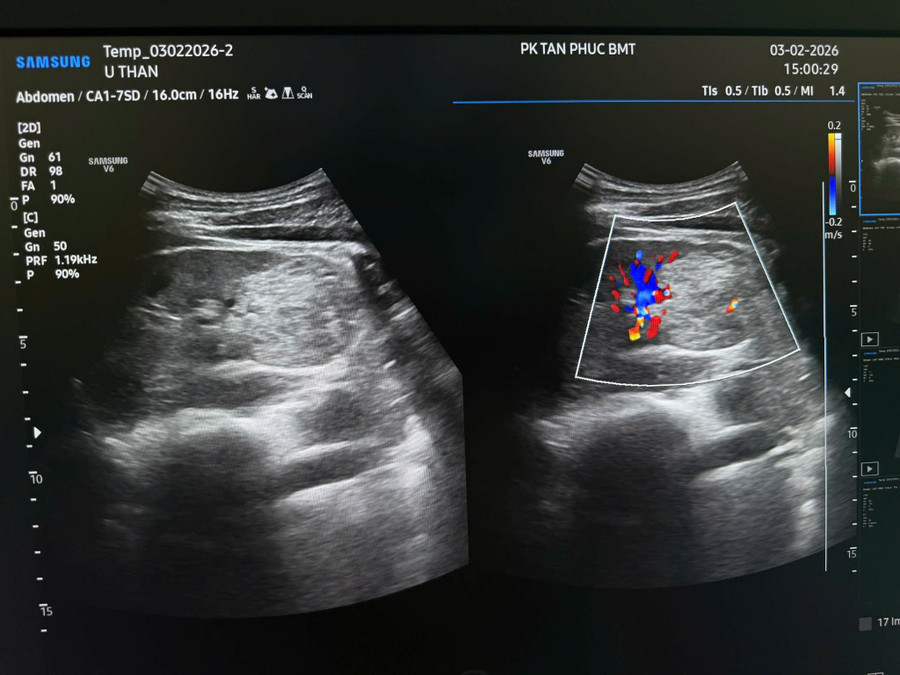

Trước đó, ngày 3/2/2026, anh P. đến Phòng khám đa khoa Tân Phúc Buôn Ma Thuột (địa chỉ 37-39 đường Lý Thái Tổ, phường Buôn Ma Thuột, tỉnh Đắk Lắk) để khám sức khỏe định kỳ.

Tại đây, anh được bác sĩ nội trú Lê Thị Trà Mi trực tiếp siêu âm.

Kết quả chẩn đoán hình ảnh cho thấy, anh P. bị tổn thương khối 1/2 dưới thận phải (RCC? Bướu máu? AML?...).

Do đó, bác sĩ Mi đề nghị chụp CTSCAN bụng có cản quang. Qua đó xác định, anh bị ung thư thận.